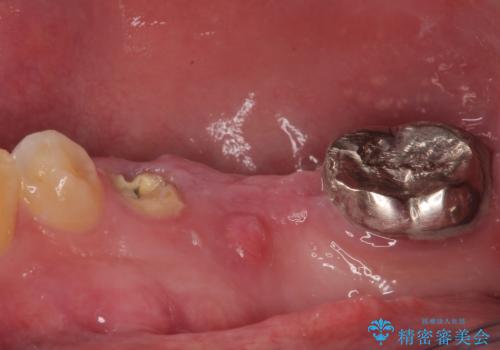

- むし歯を放置したことで、歯茎で膿が腫れ上がったしまったとのことで来院された患者様です。

ブリッジの支台歯が痛みを覚え、近医でブリッジを切断してもらって以降、そのままにしてしまったとのことでした。

問題が起きていた手前の歯から膿が出てきたことを自覚して当院を来院されましたが、既に歯根破折をしており、抜歯が必要な状態でした。

咬合力が非常に強い患者様であり、2歯欠損のブリッジ(しかも大臼歯は失活歯)は歯根破折のリスクが高すぎると判断し、抜歯部および欠損部に対して、インプラントによる補綴治療を行うこととしました。